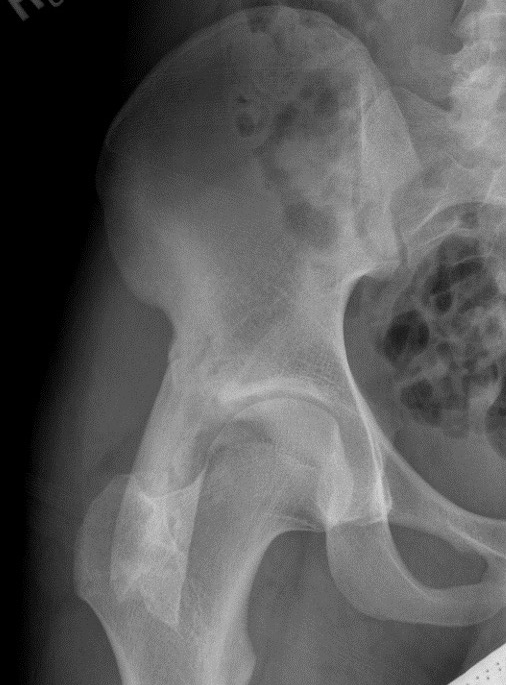

Xray

Ischial tuberosity avulsion 1Ischial tuberosity avulsion 2

Ischial tuberosity avulsion